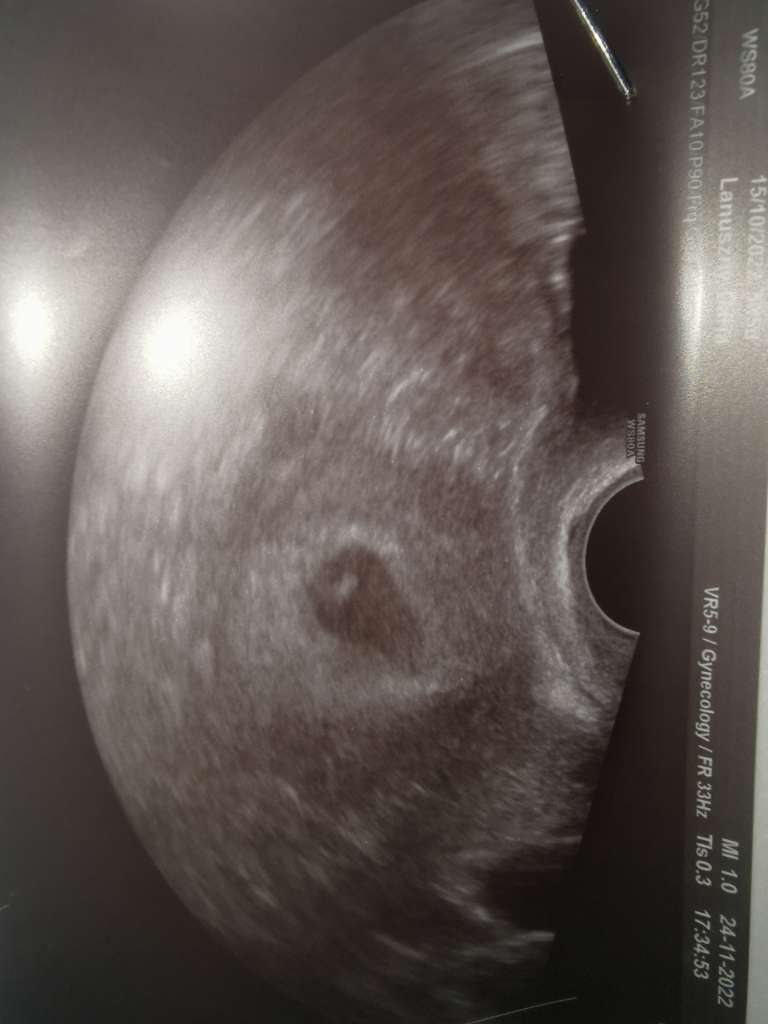

) także o 18 jechałam jak na skazanie i powtarzałam sobie że co ma być to będzie trudno nic nie poradzę przecież... Jakież było moje zdziwienie jak zobaczyłam bijące serduszko i piękny zarys rączek i nóżek

dzidziulek ma już 2cm i według dzisiejszego USG wychodzi 8tc czyli przyspieszył ze wzrostem bo według ostatniego USG powinno być 7+5